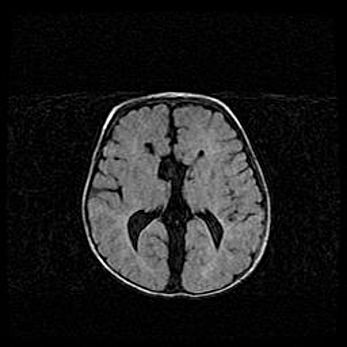

Церебральная ишемия II.

Возраст: 5 дней

Вес: 3400 г

Пол: женский

Окружность головы: 35 см

Срок гестации: 39 недель

Церебральная ишемия – это заболевание, характеризующееся недостаточностью (гипоксией) либо полным прекращением (аноксией) снабжения мозга кислородом по причине закупорки одного или нескольких сосудов. Это приводит к  что метаболическим расстройствам различной степени тяжести в тканях головного мозга, развитию коагуляционных некрозов и гибели нейронов.